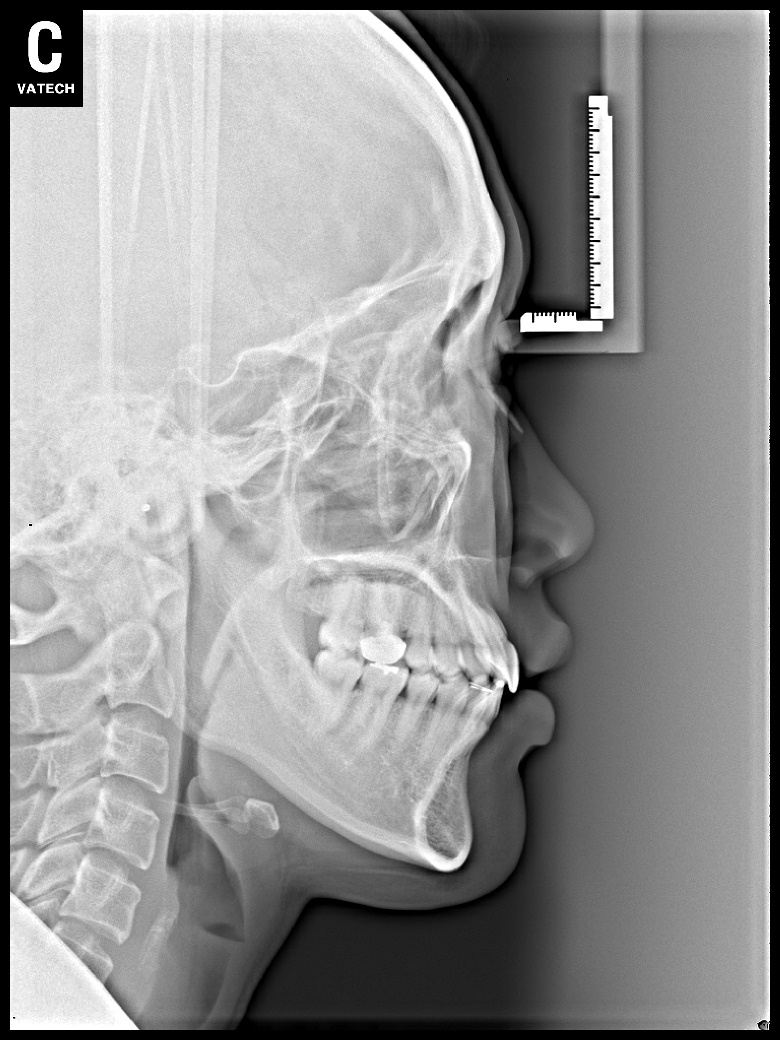

치료 전 사진입니다.